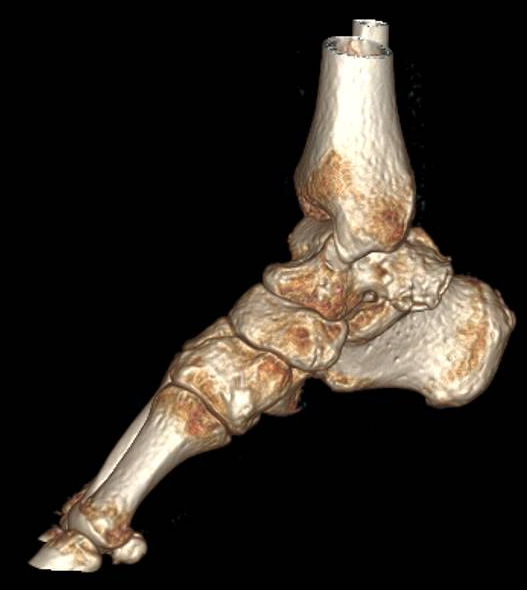

跟骨-足舟骨联合的骨化常常发生在8至12岁,而跟骨-距骨联合的骨化常常发生在12至16岁,开头所说的姚阿姨便是属于跟骨-距骨联合,也就是说姚阿姨可能在青少年的时候就已经出现了跗骨联合。并非所有的跗骨联合都会产生症状,且由于过去经济条件及对此病认识的不足,姚阿姨并没有重视,随着年龄增大,距下关节软骨退变逐渐加重,经过这一次扭伤才意外发现了此病。

箭头所示为跟距联合。

如果保守治疗无效,则可以考虑进行手术。对于跟骨-足舟骨联合来说,手术切除的疗效相对比较确切。而跟骨-距骨联合相对复杂,在制定手术方案时需要谨慎评估;一般后足力线正常、距下关节累及较少的可以考虑单纯跗骨联合切除;如果后足显著外翻、距下关节累及较多或已经出现关节退变的,可以考虑进行距下关节融合手术。本文中,姚阿姨已经出现较严重的距下关节炎,故对其进行了跗骨联合切除及距下关节融合术。